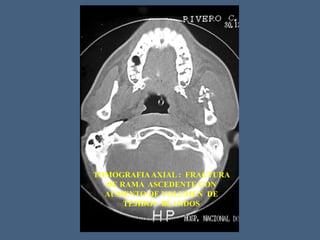

TOMOGRAFIAAXIAL : FRACTURA

DE RAMA ASCEDENTE CON

AUMENTO DE VOLUMEN DE

TEJIDOS BLANDOS

TOMOGRAFIAAXIAL : FRACTURA DERAMA ASCEDENTE CON AUMENTO DE VOLUMEN DE TEJIDOS BLANDOS